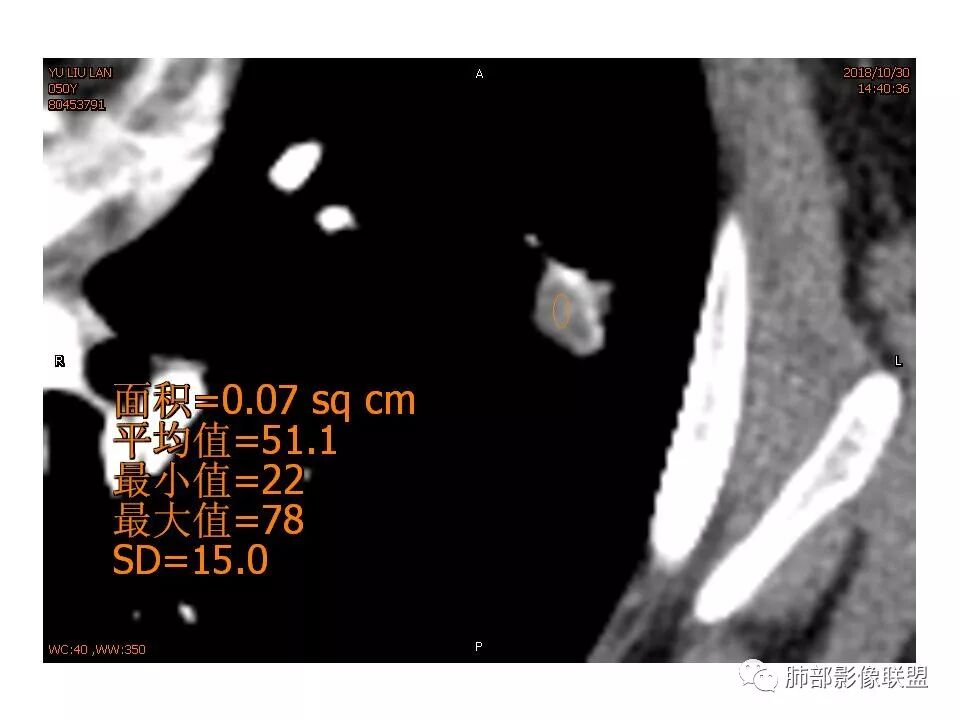

女,50。实性不规则结节,大小12*13mm,分叶、毛刺、胸膜凹陷,牵拉力强,增强渐进性强化,动脉期强化20,静脉期还有进一步强化。边缘强化,点状坏死。

其内血管被破坏。

@马宁强杨凌示范区医院放射科 ,不一定准确,看不见血管走行,强化不均匀,有点状第密度。

请问南边老师,这个进入结节的血管算增粗吗?

南边:

稍增粗

恶性征像,胸膜牵拉,浅分叶,毛刺,增强强化明显,净增超25hu。血管边缘模糊串珠样改变。